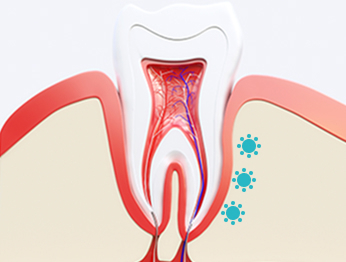

コルチコトミー(Corticotomy)は、

歯の周りの骨にやさしい刺激を与えることで、

歯の動きを早めるための処置です。

• #歯槽骨に軽い刺激

局所麻酔を行い、

硬い歯ぐきの骨(歯槽骨)に

やさしい刺激を与えます。

コルチコトミー受け口矯正のポイントは、 歯槽骨、特に歯ぐきの骨の表面に 適切な刺激を与えることです。

外科的な方法で歯の周りの骨に刺激を加えることで、 骨を一時的に柔らかい状態にします。

その結果、骨の働きが活発になり、 大人になってから固定された歯でも より動かしやすくなります。

この反応は医学的に RAP(リージョナル・アクセララトリー・フェノメノン) と呼ばれています。